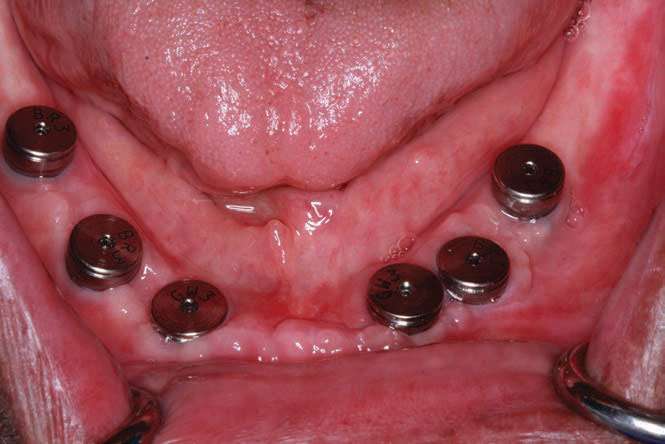

The BioHorizons implants were placed with a good A-P spread, and the bone in the anterior mandible was left in case it was needed at the uncovery appointment (Figure 8). At the uncovery visit, the LightScalpel laser was used to perform a trephine of the posterior implants by placing the surgical guide, marking the osteotomy sites with a Dr. Thompson’s marking stick, and (using a super-pulsed 2W setting) to gently remove the cuff of tissue over the implants (Figure 9). In the anterior mandible, a full-thickness flap was done, and the remaining bone was removed with the PIEZOSURGERY device (Figure 10). The peri-mucosal healing abutments were placed, and a soft-tissue conditioner was placed in the lower denture (Figure 11). After one month of healing, the patient was ready for impressions (Figure 12).

The 3-in-1 abutments are included with the Tapered Internal Dental Implants (BioHorizons) and, when a ball-top screw is placed, these become impression copings (Figure 13a). The initial ball-top screw impression was taken (Aquasil Ultra Xtra Plus [Dentsply Sirona Restorative]) (Figure 13b). This impression material has excellent wettability and tear strength for capturing the subgingival abutment implant interface. The setting time of 5.5 minutes gives adequate working time and is appropriate for larger cases for which an extended working time is desirable.